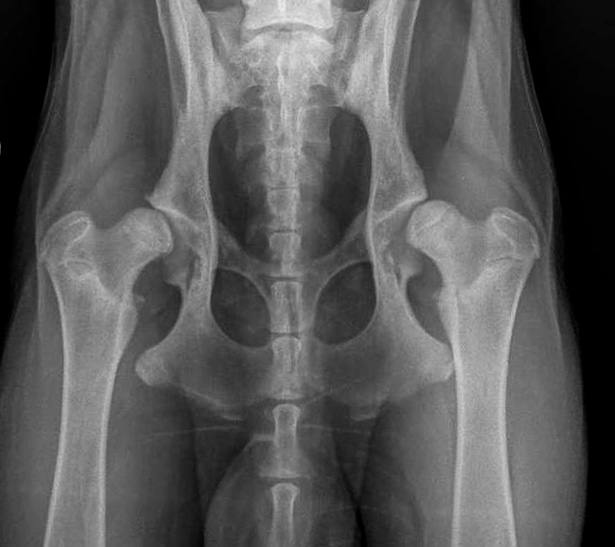

Hier nun einige HD Röntgenbilder:

HD frei / HD- A / HD-0 / HD-normal |

| HD:E/HD-schwer/HD 4-5 |

A |

= HD-frei |

HD-0 |

normal |

Normal, unauffällige Gelenke, NORBERG-Winkel von 105 Grad oder mehr |

B |

= Übergangsform |

HD-1 |

fast-normal |

Fast normal, geringe Veränderungen an Kopf oder Pfanne, NORBERG-Winkel von mindestens 100 Grad |

C |

= Grad1 (leicht) |

HD-2 |

leicht |

Leichte Inkongruenz, divergierender Gelenkspalt, NORBERG-Winkel um 100 Grad |

D |

= Grad2 (mittelgradig) |

HD-3 |

mittel |

Gravierende Veränderungen mit arthrotischen Zubildungen, NORBERG-Winkel zwischen 90 und 100 Grad |

E/1 |

= Grad3 (schwer) |

HD-4 |

schwer |

Das gesamte Gelenk ist stark verändert, evtl. eine vollständige Luxierung, NORBERG-Winkel unter 90 Grad |

E/2 |

= Grad4 (sehr schwer) |

HD-5 |

sehr schwer |